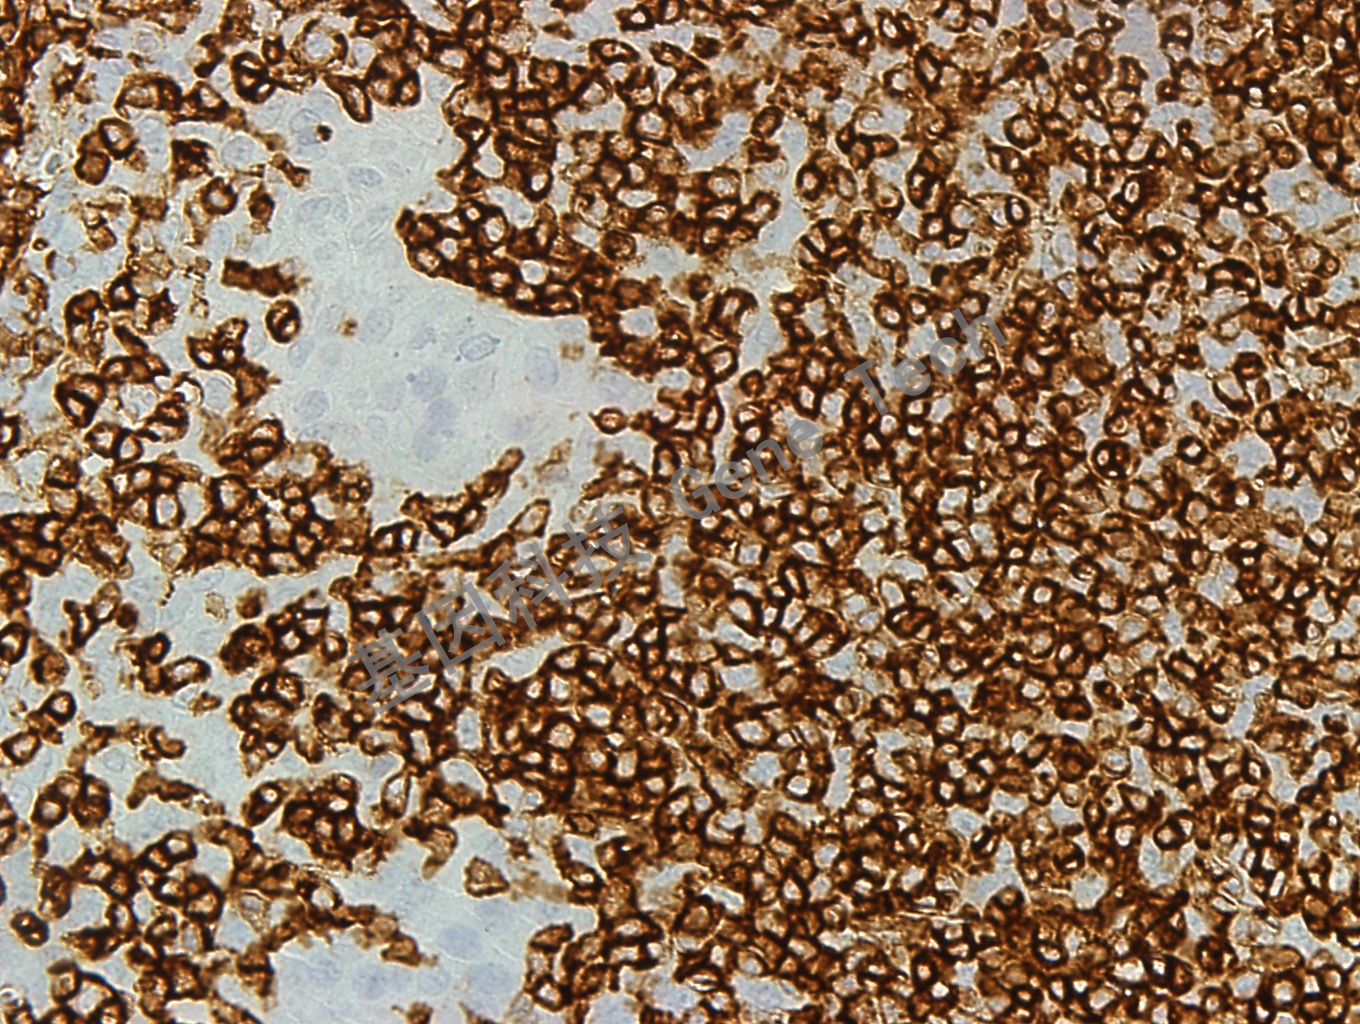

| 克隆號:PD7/26 | 陽性對照:扁桃體 | 陽性部位:細胞膜 |

| 預處理:高pH熱修復 | 適用:石蠟切片/冰凍切片 | 顯色系統(tǒng):GTvisionTM |

| 簡介:人淋巴細胞表面的CD45 分子因其剪切形式不同有5 中蛋白形式依次為:CD45RO、RB、RA、RBC 和RABC,其分子量(不計糖鏈)分別是180、190、195、205 和220kDa。其中CD45RB 表達在B 細胞、某些T 細胞亞群、單核細胞、巨噬細胞中,粒細胞中表達較弱。CD45 抗體PD7/26 克隆是出現(xiàn)于上世紀80 年代初經(jīng)典克隆, 能夠與5 種CD45 蛋白的3 種類型 (分子量為 190,205 和220 kDa)結(jié)合。其提示意義基本同CD45,但在Langerhan’s 細胞與小部分T 細胞中不表達。 | ||

| 扁桃體石蠟切片,用 CD45RB(GT2219)染色,細胞膜陽性,DAB 顯色。(40X) | ||